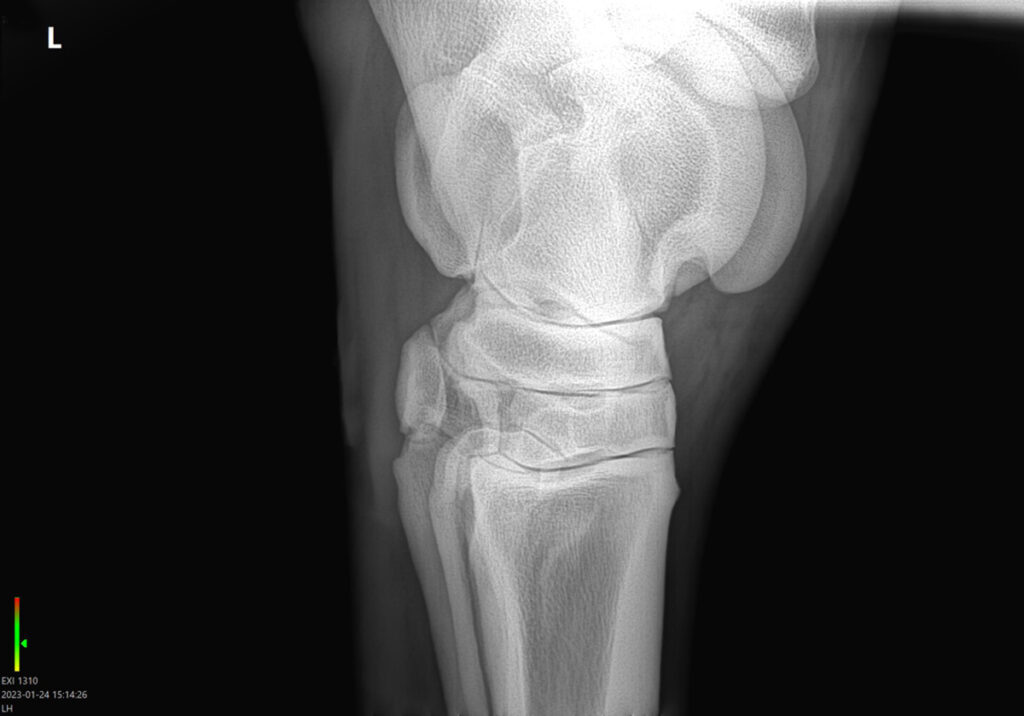

Artróza je degenerativní onemocnění vznikající z důvodu nadměrného opotřebení chrupavky tvořící styčnou plochu mezi klouby. Dochází k postupné destrukci kloubní chrupavky a následné tvorbě drobných kostěných výrůstků neboli osteofytů. Artróza často postihuje velké nosné klouby končetin.

Jedním z nejdůležitějších kroků v léčbě onemocnění kloubů je diagnostika povahy a lokalizace problému. To může být jednoduché je-li kloub viditelně oteklý a bolestivý, avšak časté jsou i případy, kdy skryté kloubní onemocnění stojí za zhoršenými výkony koní. Zde nastupuje detailní diagnostika s využitím rentgenu, ultrazvuku, případně pokročilých zobrazovacích technik, jako je například jaderná scintigrafie nebo magnetická rezonance.